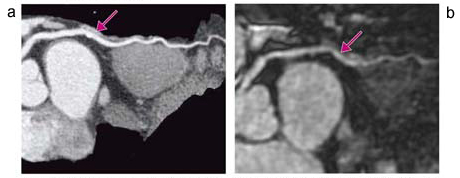

図1 70歳,男性(胸痛)

a:MDCTのcurved MPR像では,LCX 中間部に高度石灰化(↓)があり,狭窄病変の評価が困難であった。

b:MRCAのcurved MPR像では,同部分が石灰化の影響を受けずに明瞭に描出され(↓),高度な狭窄は認められなかった。